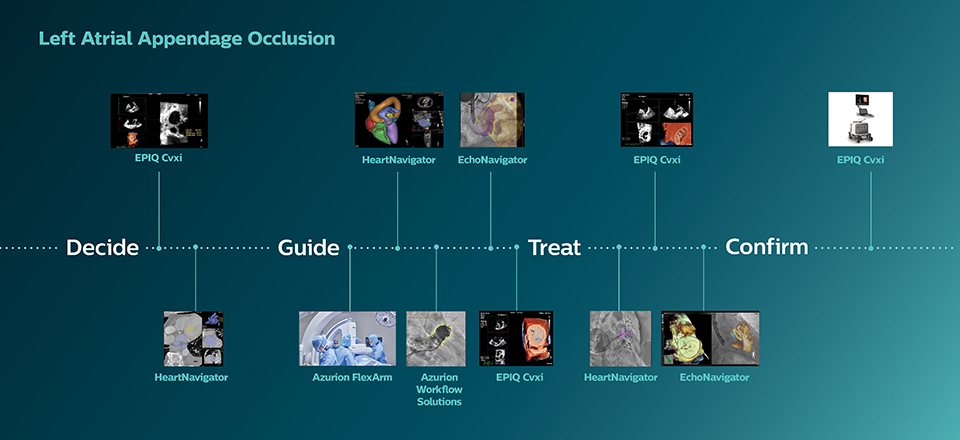

Highlighted products for this procedure

Azurion 7 M20 with FlexArm image-guided therapy system

EPIQ CVxi interventional ultrasound system

EchoNavigator

HeartNavigator

Clinical solutions for treating structural heart diseases

Azurion workflow solutions

The Azurion has been specifically designed to integrate information from multiple sources and to save procedure time through flexible and user-centric display and control options. For example: